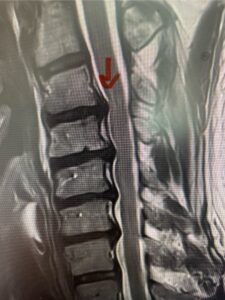

In this next case, this patient is a 47 year-old female who presents with intractable low back pain with severe pain, numbness, and weakness in the right lower extremity that had gotten progressively worse over a year. The patient had failed conservative management including physical therapy and epidurals. She was noted to have ⅘ weakness of plantar flexion. MRI demonstrated a large right L5-S1 disc herniation with severe compression of the descending right S1 nerve root (Fig 3). It was decided to perform a right L5-S1 hemilaminectomy for removal of the disc fragment and decompress the S1 nerve root. When you expose the disc, one must be certain to release any anterior adhesions to the nerve root in order to prevent a dural tear during retraction of the nerve root. It is also important to make sure during exposure and you finally encounter the dura after removing the ligamentum and fat, to make sure you are looking at the nerve root and not the main trunk of the thecal sac because if you don’t you can avulse or damage the nerve root if you retract the wrong structure.

Fig. 3a: Sagittal and axial T2-weighted lumbar MRI images demonstrating large right L5-S1 disc herniation (red arrows)

Fig. 3b

We found a massive subligamentous herniation which had to be revealed by having your partner retract the freed nerve root with a nerve root retractor and putting slight downward pressure on the more medial and anterior disc space. There is nothing more satisfying when the jelly (disc fragment) of the annulus (donut) comes squirting out and you remove a large chunk of disc material that clearly was stretching the ligament membrane and compressing the nerve root. This does cause back pain in addition to radiculopathy not only by the component of mechanical compression but also the stretching of the nerves within the ligament. We performed this surgery and noted that the nerve root was a very angry red color or hyperemic and we removed a large subligamentous fragment. The patient had improvement of her preoperative radicular symptoms.